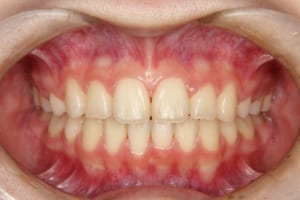

治療後

| 治療内容 | 子どもの矯正治療(前期治療) マルチブラケット装置を使用した大人の矯正治療(後期治療/成人矯正治療)を行いました。 |

| 治療期間 | 子どもの矯正治療:2年1か月 大人の矯正治療:2年4か月 |

| 抜歯および非抜歯 | 上顎:両側第一小臼歯 下顎:右側第二小臼歯 先天欠如:下顎左側第二小臼歯 乳歯:下顎左側第二乳臼歯 |